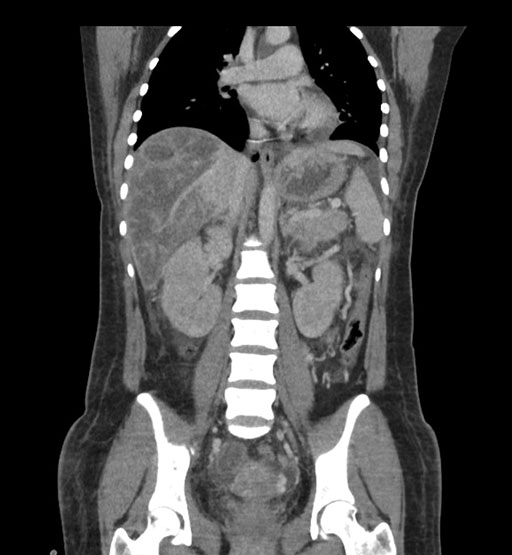

Coronal Arterial